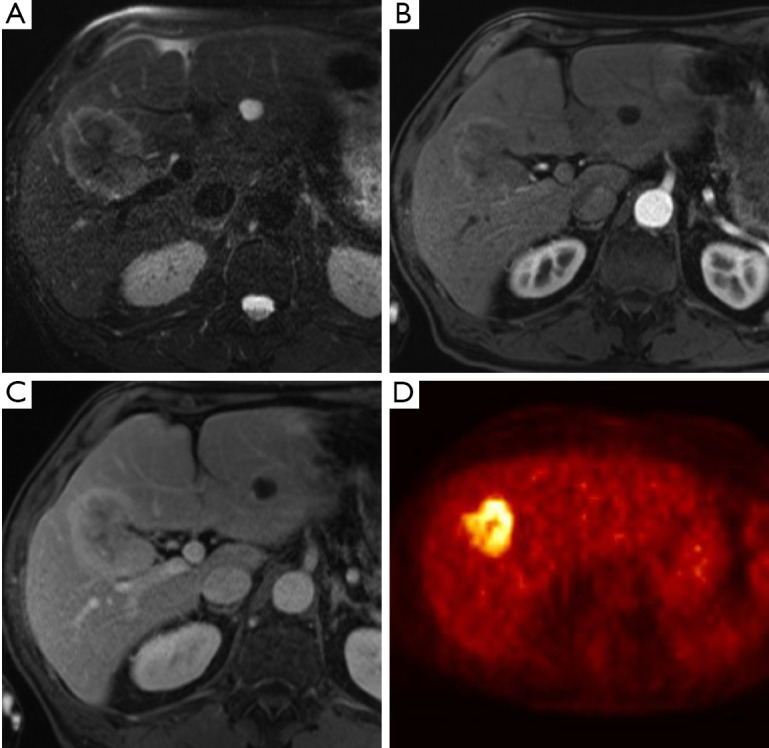

- Risonanza Magnetica (RM) e colangiopancreatografia a risonanza magnetica (CPRM): queste tecniche stanno guadagnando sempre più favore. La RM offre un’eccellente risoluzione di contrasto dei tessuti molli, mentre la CPRM fornisce una visualizzazione non invasiva e dettagliata dell’albero biliare, paragonabile alla colangiografia diretta. La combinazione di RM e CPRM ha un’accuratezza di circa l’80% nel predire la resecabilità ed è particolarmente vantaggiosa per la stadiazione biliare, definendo l’estensione del tumore lungo i dotti.

- PET/CT: il ruolo della tomografia a emissione di positroni (PET) con TC nella valutazione della resecabilità locale è limitato. Tuttavia, questa modalità è molto utile per rilevare metastasi a distanza e linfonodali non identificate da altre tecniche, con una specificità superiore all’80%. Il suo utilizzo può quindi prevenire laparotomie non necessarie in pazienti con malattia metastatica occulta.